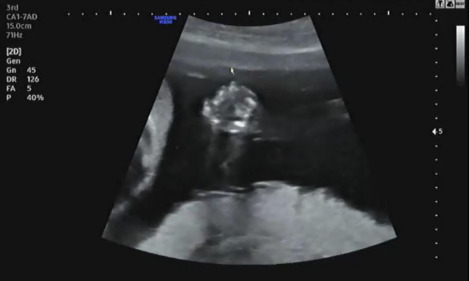

다음은 양쪽 눈 모두 눈동자의 여부를 확인한다. 왼쪽, 오른쪽 순서대로 태아의 눈동자가 있는지 확인했다. 눈을 감고 있는 태아의 눈동자까지 확인이 가능한 것이 더욱 신기했다.